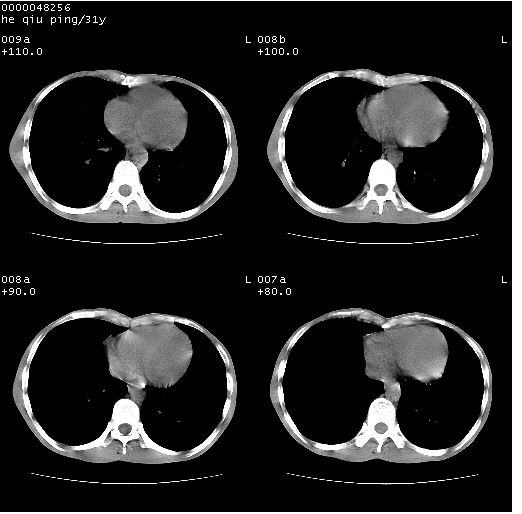

双上肺多发空洞,双飞散在分布大小不一的片状结高密度影节状大片状高密度影。符合结合肉芽肿形成及空洞形成。

双侧弥漫性病变,双上叶尖后段、下叶北段见多个空洞,多见于结核感染。右中叶及双下叶斑片状,结节状影,考虑为肉芽肿形成及支气管播散。但由于患者消瘦体质,抵抗力低下,若继发感染,如金葡菌肺炎也有可能。

两肺继发性结核伴多发空洞形成!不除外合并霉菌感染!

肺结核伴空洞形成继发霉菌感染?结合痰菌检查!